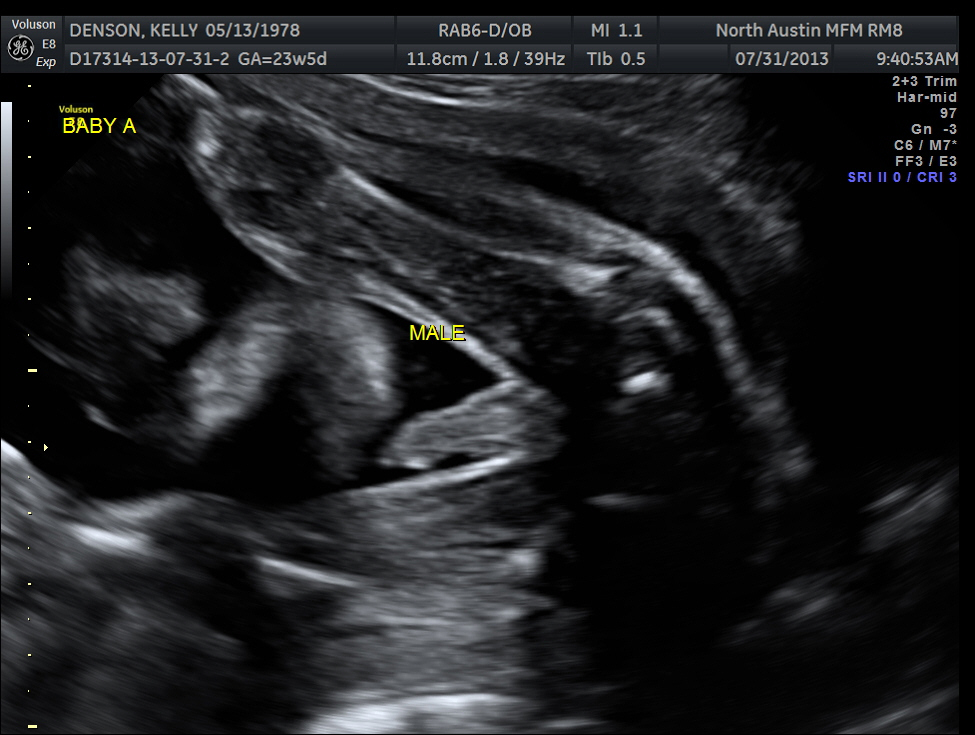

Ultrasound pics

Yesterday was my growth scan with Dr. Haeri. I'll do a second post with a full update in a minute-- first, here are the pics I got (on a CD, so better quality than the prints). C was the star of the show this week and poor Miss B got left out. But pretty neat to see some of the 3D images now!

Baby A:

Baby A is breech, as he has been pretty much the entire time. He and I are going to have to talk about that, because I need him to be head down. You hear that, Mr. Man? It's time to stop sitting on my cervix and get your head down there. But he is still a big boy. He weighs 1 lb., 8 ounces and is in the 64th percentile as compared to singletons (where 50% is average).